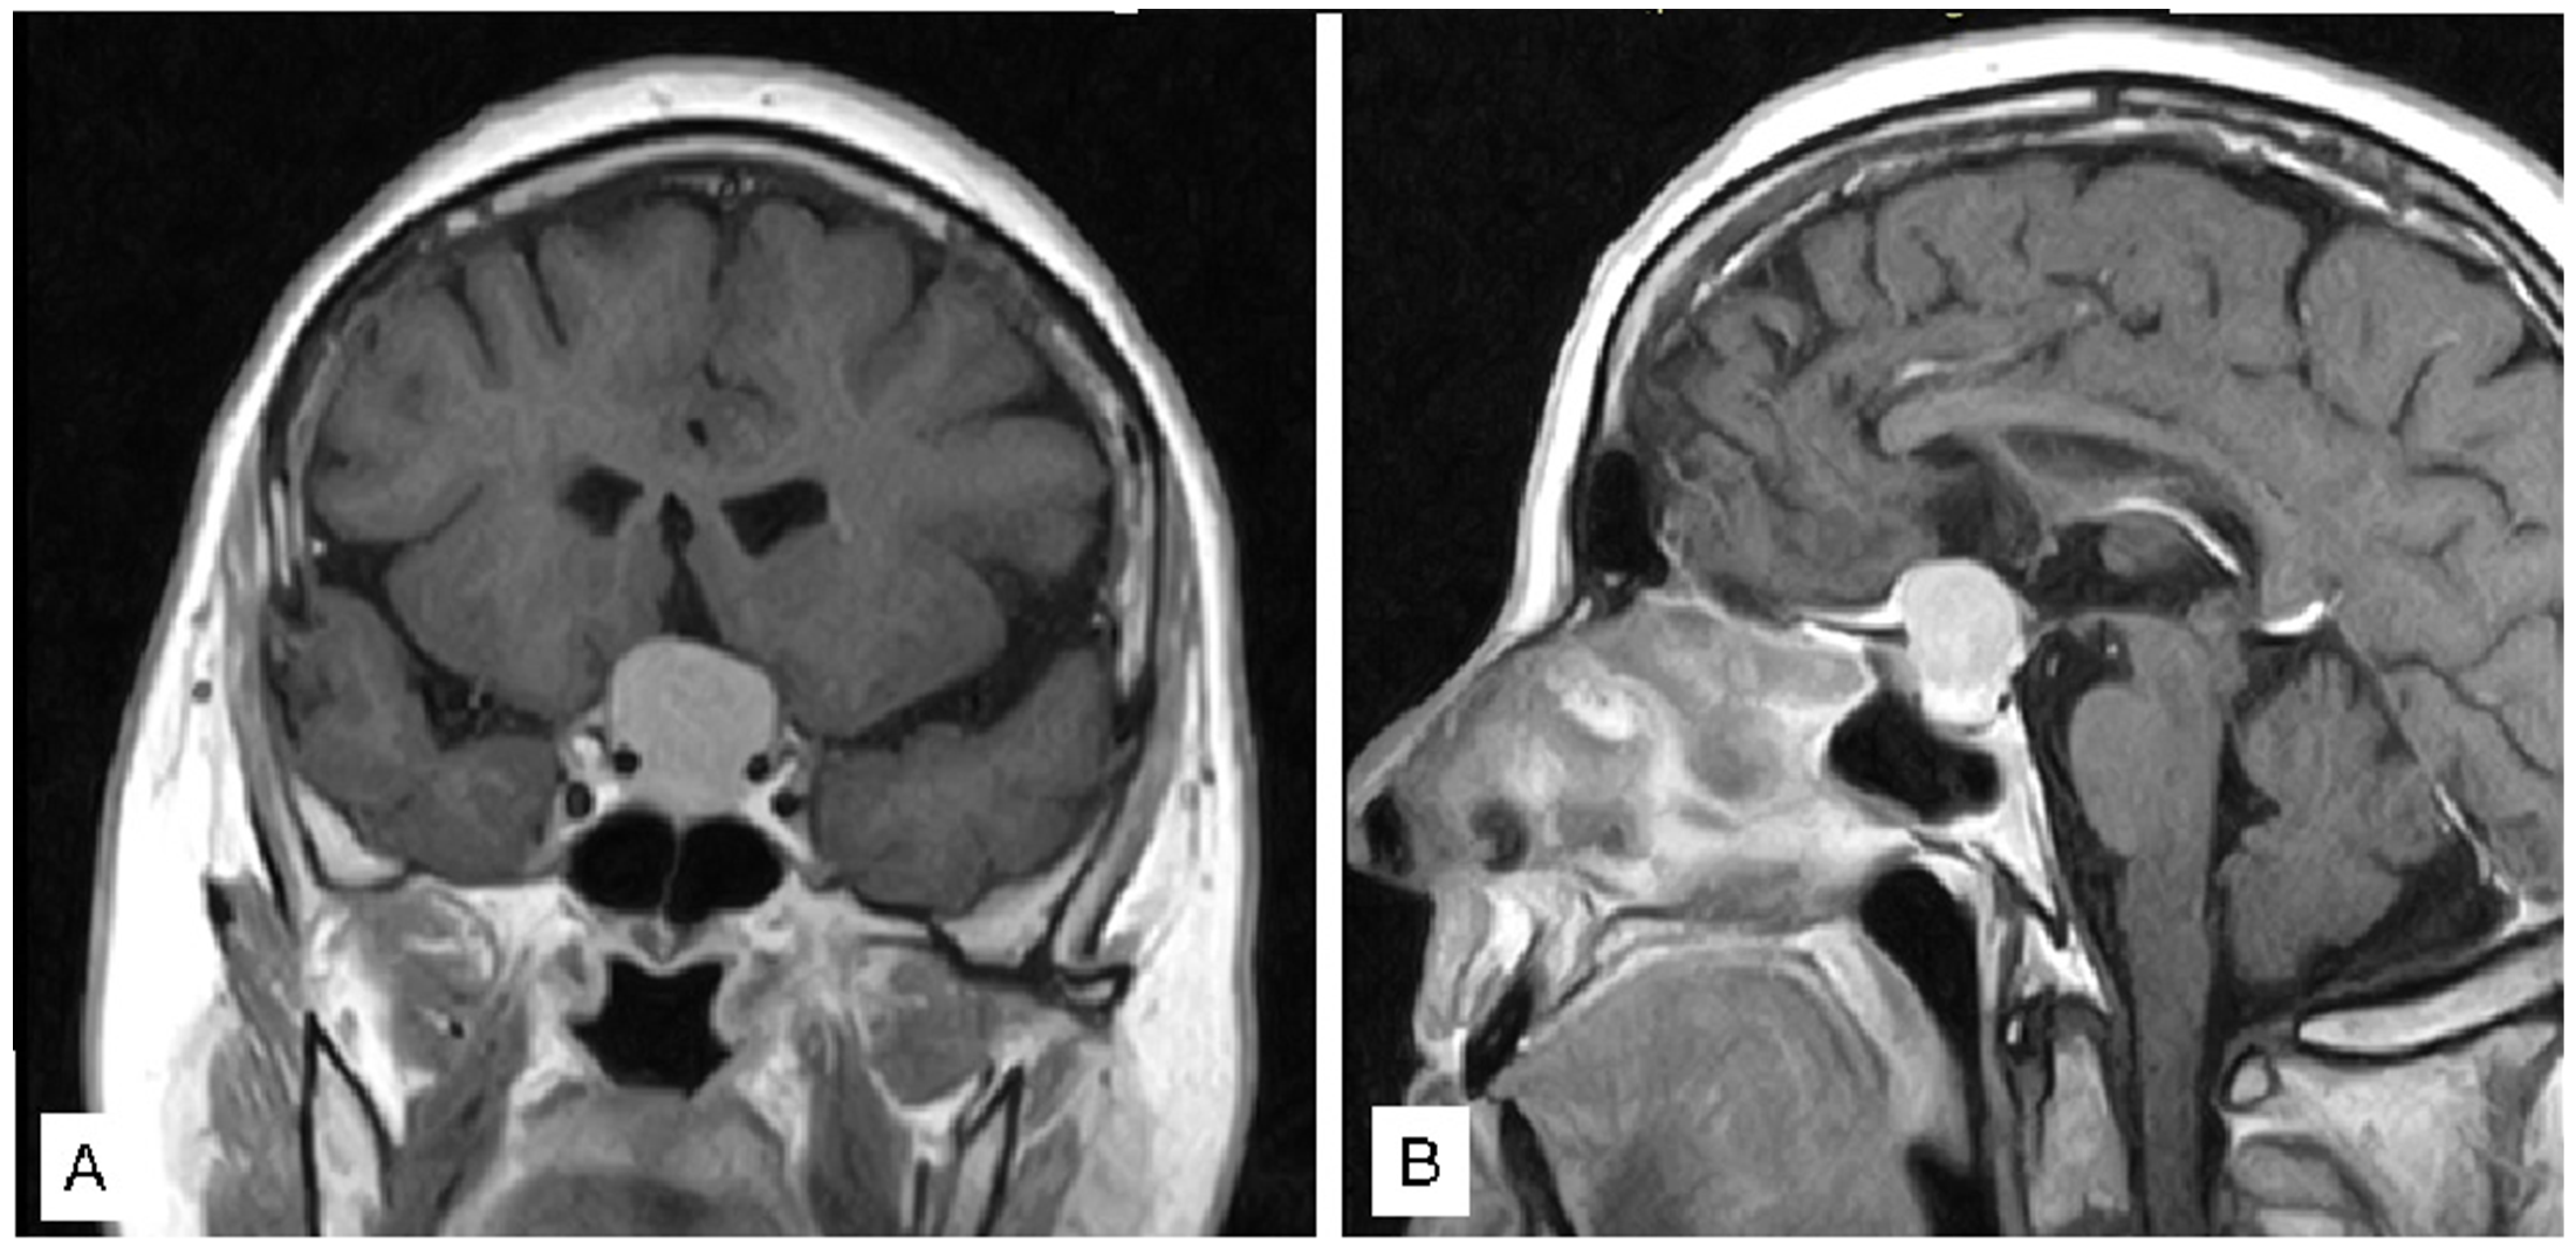

3.1.1. Case 1